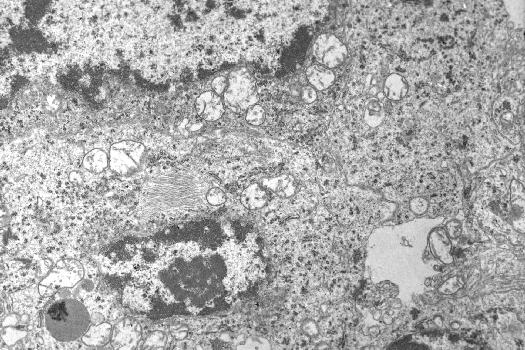

2. Electron microscopic features of the human

pinealocytes

AUTHOR'S NOTE: Although the specimens were taken at autopsy within 5 hours of death

(mean 2.5 hours), the post mortem degeneration of membranous ultrastructures

cannot be ignored in the electron micrographs of human materials.

Paired twisted filaments in a human pineal parenchymal cell

(in the center left, original x9,300)